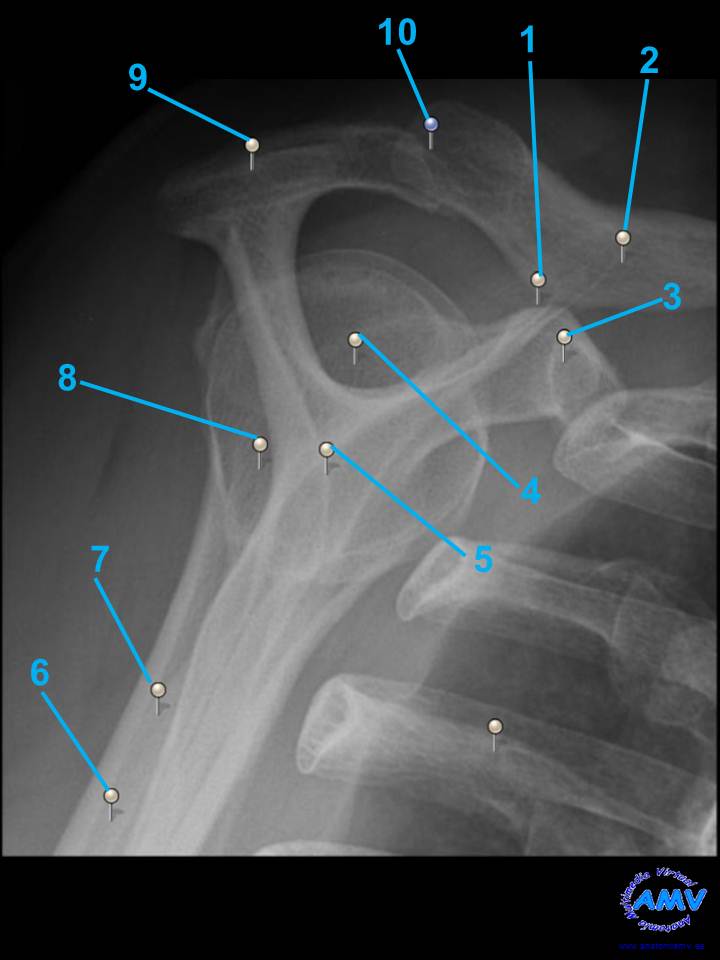

Radiografía del Hombro III

rx_ms_04.jpgIndique que estructura se señala con el número correspondiente:

El nº 1 señala .

El nº 2 señala .

El nº 3 señala .

El nº 4 señala .

El nº 5 señala .

El nº 6 señala .

El nº 7 señala .

El nº 8 señala .

El nº 9 señala .

El nº 10 señala .